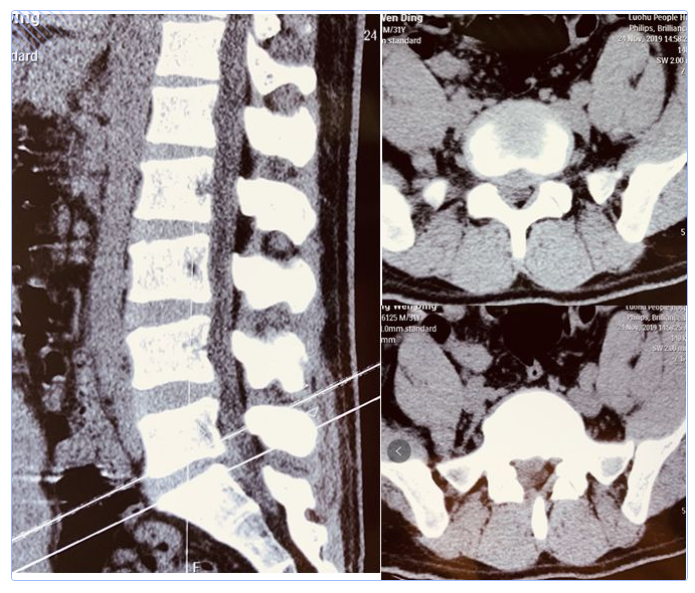

何教授听完了姜先生曲折的求诊经历后,为他感到揪心,也非常重视。立即为他安排了住院治疗,并且完善了相关检查。检查后CT发现,姜先生的腰5骶1右侧有巨大型突出,严重压迫了右侧神经根。

MRI检查更证实了姜先生的腰5骶1有巨大型椎间盘脱出,偏下偏右,压迫了椎管及右侧神经根。